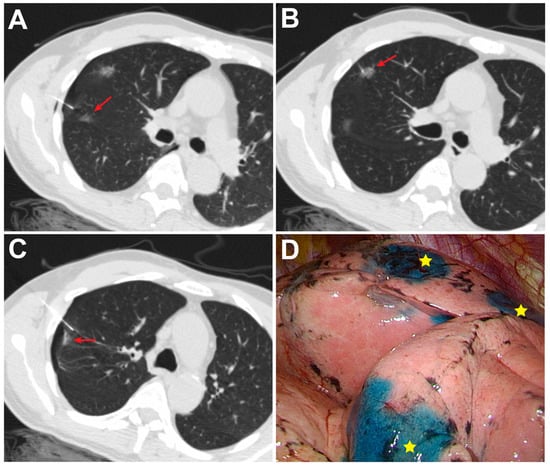

2.2. CT-Guided PBD Localization

2.3. Success Rate and Complications

2.4. VATS after Localization